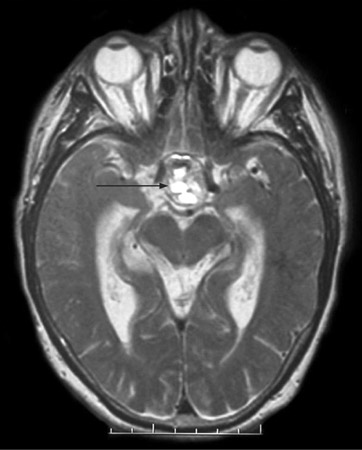

[Figure caption and citation for the preceding image starts]: T2-weighted axial MRI scan showing a lesion in the pituitary fossa (arrow), displaying heterogeneous signal intensity suggesting recent apoplexyBMJ Case Reports 2009; doi:10.1136/bcr.09.2008.0902 [Citation ends].